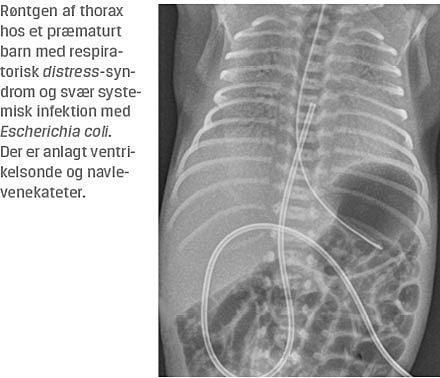

II. En dreng, der var født i uge 29 + 4 dage med en fødselsvægt på 1.200 g, var respiratorisk påvirket umiddelbart efter fødslen. På mistanke om respiratorisk distress-syndrom og infektion fik han surfaktant, og der blev udført bloddyrkning og påbegyndt et sepsisregime som beskrevet ovenfor. Drengen rettede sig klinisk, men ca. 26 timer efter behandlingsstart blev han svært påvirket med bleghed og stort iltbehov. Der blev påbegyndt meningitisbehandling, og han blev intuberet samt flyttet til et universitetshospital. I forbindelse med overflytningen kom svaret på drengens bloddyrkning, der viste ampicillinresistente, men gentamicinfølsomme E. coli. I moderens urin blev der påvist samme bakterie med samme resistensmønster. Overraskende påviste man ved en lumbalpunktur efterfølgende meningitis forårsaget af E. coli, der var resistent for både ampicillin og gentamicin. Drengen døde efter få døgn af komplikationer i forbindelse med den svære infektion.